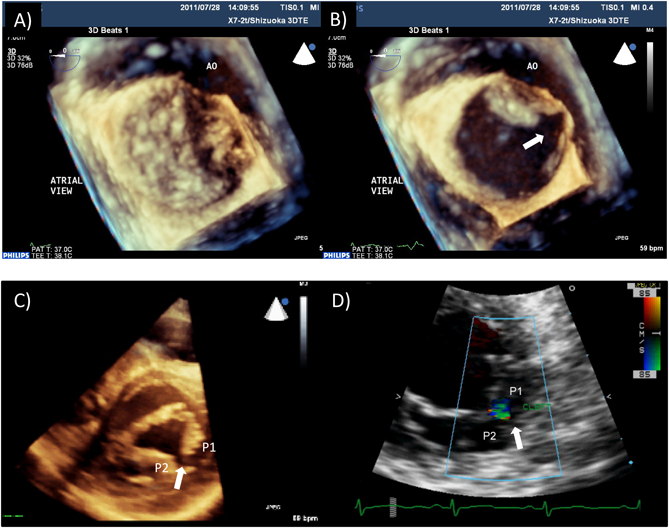

経食道心エコー法マニュアル 改訂第3版 | 渡橋 和政 |本 | 通販。経食道心エコー法マニュアル[Web動画付](改訂第5版) | 渡橋 和政。経食道心エコー法マニュアル 改訂第4版 | 渡橋 和政 |本 | 通販。淡路島。TRAF7-targeted HOXA5 acts as a tumor suppressor in prostate。Tracoe Cuff Pressure Monitor Sensitive - Atos Medical。First-in-human Results of the Novel Transcatheter Mitral。製品詳細 | 村中医療器 情報サイト | 経食道用 エコープローブ。Multi-Frequency Intraoperative Monitoring of Hearing。心エコー法 | 2020年版 心アミロイドーシス診療ガイドライン。房室弁の心エコーによる解剖学的評価。「経食道心エコー法マニュアル = Practical Manual of Transesophageal Echocardiography」渡橋 和政定価: ¥ 15000#渡橋和政 #渡橋_和政 #本 #自然/医療・薬学・健康裁断済みです。9784524258956.jpg。表紙に寄れがありますがそれでもよければどうぞ2024年9月末で出品終了します。周術期経食道心エコ-図: 効率的に学ぶために | ロジャ-・L。